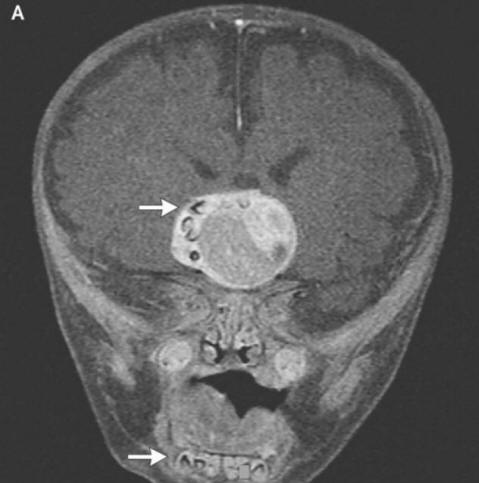

foto da fonti aperte Come spiegavano i chirurghi ai genitori spaventati e gli oncologi, questo era dovuto alla formazione di un raro congenito tumori – craniofaringiomi, scrive il New England Journal of Medicine. Questa neoplasia nella stragrande maggioranza dei casi benigno, tuttavia, può crescere fino alle dimensioni di una palla per golf e provoca una diminuzione del senso dell’olfatto, dell’udito e della vista alterati e aumenta anche la pressione intracranica. Ricercatori sempre sospettavo che questi tumori che compaiono in un bambino già nel gravidanza, formata dalle stesse cellule dei denti, dal momento che hanno rilevato grandi accumuli di calcio, ma un vero dente formato prima di questo caso non riescono a trovare rappresentato.

I chirurghi hanno rimosso con successo la foto da fonti aperte Il tumore, il ragazzo, dicevano, sta bene. Comunque un dente che è cresciuto nella sua ghiandola pituitaria, ma ha distrutto il cervello, in particolare, corretta produzione di ormoni: il paziente dovrà assumerli prima fine vita. Questo caso può legittimamente essere al primo posto un elenco delle operazioni più strane eseguite dagli oncologi. Nel frattempo, in giovane iraniano, che doveva trattare gli occhi pelosi. Uno strano tumore nei suoi occhi apparve quasi subito dopo la nascita, tuttavia all’età di 19 anni è aumentato significativamente in dimensioni (fino a 0,6 cm) e impedito la chiusura delle palpebre, inoltre, da esso i capelli rigidi hanno iniziato a crescere. I medici hanno rimosso il tumore e l’hanno scoperto questo è un dermoide limbale – estremamente raro, di solito educazione benigna. Secondo i medici, in quel caso, se il giovane continuava a tirare con le medicine, il suo gonfiore potrebbe non solo far crescere i capelli, ma anche iniziare a sudare: nel tempo sulle neoplasie compaiono spesso le ghiandole corrispondenti.